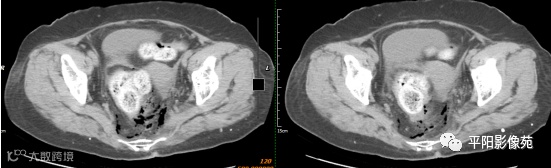

影像表现:乙状结肠前方可见不规则条状软组织密度影,边界不清,内见点状高密度;乙状结肠周围及骶前可见多发气体密度影。

影像表现:主要特点是腹腔内游离气体,可见肠壁增厚,边缘模糊,周围脂肪间隙模糊不清,并见不规则片状低密度,有粪石漏出时可见结节状高密度。